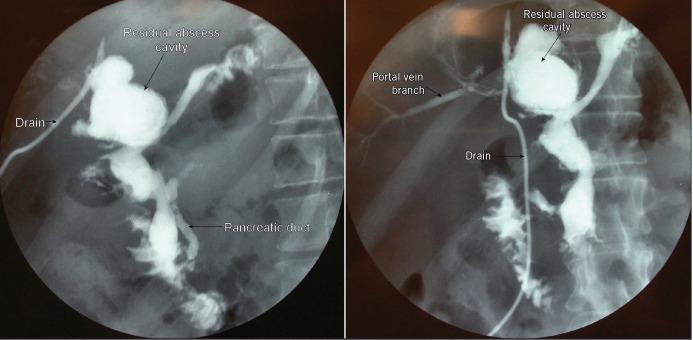

Pseudocyst formation following acute and chronic pancreatitis is a well known complication. A pancreatic pseudocyst fistulating into the portal vein is a rare and potentially fatal complication. We report a case of pancreatic pseudocyst - portal vein fistula, which was managed with a conservative approach.

急性和慢性胰腺炎后形成假性囊肿是一种众所周知的并发症。胰腺假性囊肿向门静脉内破溃是一种罕见且可能致命的并发症。我们报告一例胰腺假性囊肿 - 门静脉瘘病例,该病例采用保守方法治疗。